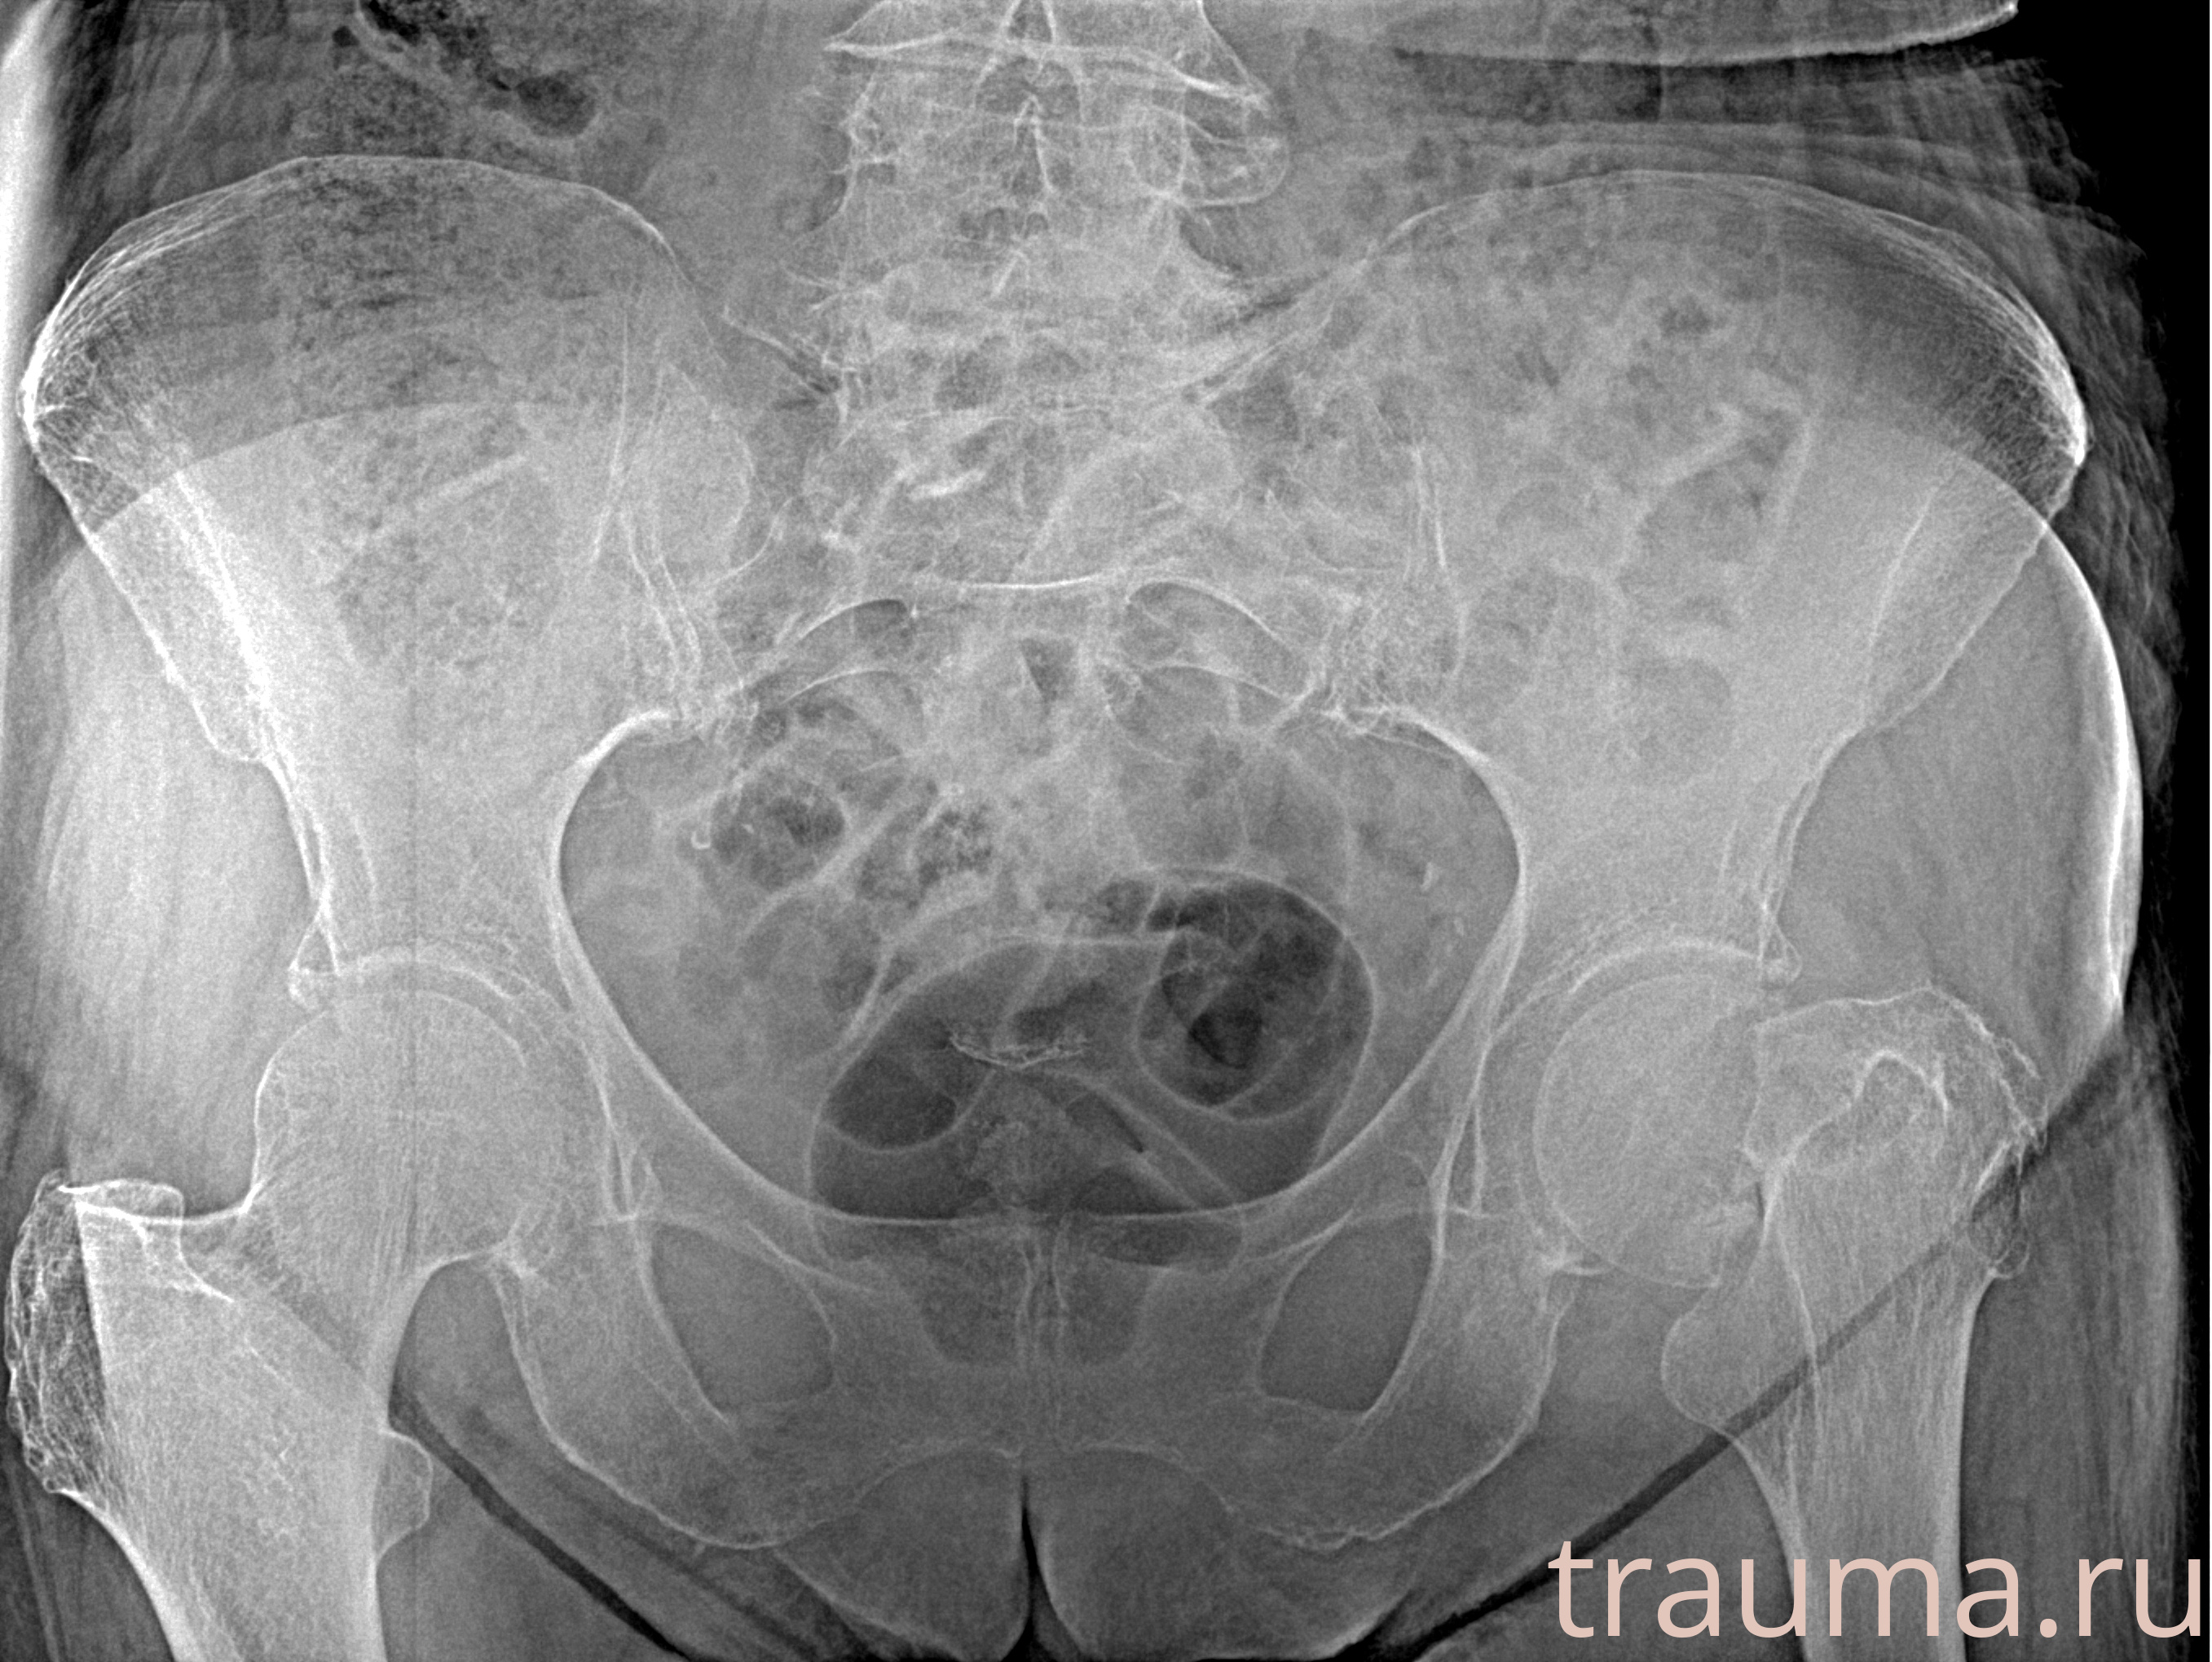

Рентген на дому: по вашему адресу приезжает врач-рентгенолог, травматолог-ортопед с мобильным рентгеновским аппаратом, проводит диагностику травмы или заболевания, делает необходимые рентгенограммы, дает рекомендации по дальнейшему лечению. Получить качественные снимки в домашних условиях возможно благодаря уникальной методике, разработанной МосРентген Центром для института  Склифосовского